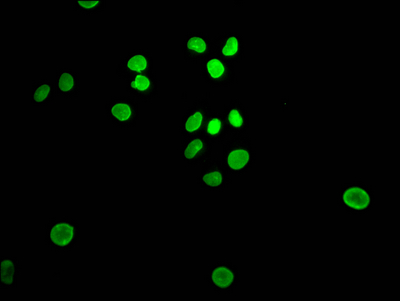

IHC staining of FFPE human bladder carcinoma with recombinant Retinoblastoma antibody (clone RB1/7080R). HIER: boil tissue sections in pH9 10 mM Tris with 1 mM EDTA for 20 min and allow to cool before testing.